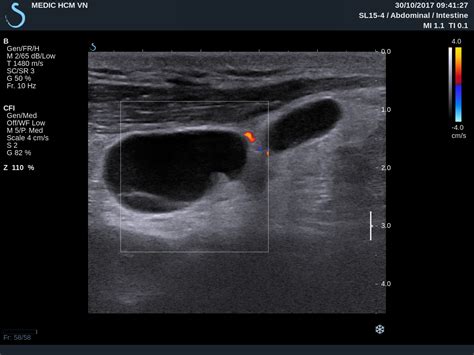

• Blood Flow Patterns: Using Doppler technology, radiologists can assess how blood flows into the node. Abnormal vascularity is often a key marker for pathology.

The radiologist analyzes the ultrasound images to generate a report for your primary physician. It is important to remember that an ultrasound is not always definitive. While it is excellent at identifying suspicious features, it cannot confirm a diagnosis like lymphoma or metastatic cancer on its own. If the ultrasound shows concerning features, a fine-needle aspiration (FNA) or a core biopsy may be recommended to obtain a tissue sample for laboratory analysis.